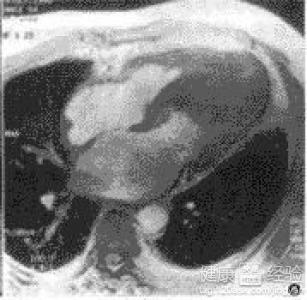

摘要:關(guān)于擴張性心肌病的最新治療,小巷深處的隱藏寶藏正逐漸為人們所發(fā)現(xiàn)。通過先進的醫(yī)療技術(shù)和方法,擴張性心肌病的治療取得了新的進展。這些治療方法旨在改善心臟功能,提高患者生活質(zhì)量。小巷深處的醫(yī)療機構(gòu)或?qū)<铱赡茈[藏著寶貴的治療經(jīng)驗和方法,為尋求最佳治療方案的病患帶來希望。更多詳細信息需要進一步探索和研究。

擴張性心肌病是一種嚴重的心臟疾病,但“心之港灣”為你帶來希望,這里的專家團隊一直在深入研究擴張性心肌病的最新治療方法,并深知每位患者都渴望得到最佳的治療和關(guān)懷,他們努力不懈,為患者帶來生機和新生。

你將了解到最新的藥物治療、心臟康復(fù)計劃以及生活方式調(diào)整等方面的知識?!靶闹蹫场边€開展了一系列臨床試驗,為患者提供最新的治療方案,他們的治療方法全面且個性化,因為每個患者的狀況都是獨特的,所以需要因人而異定制治療方案。